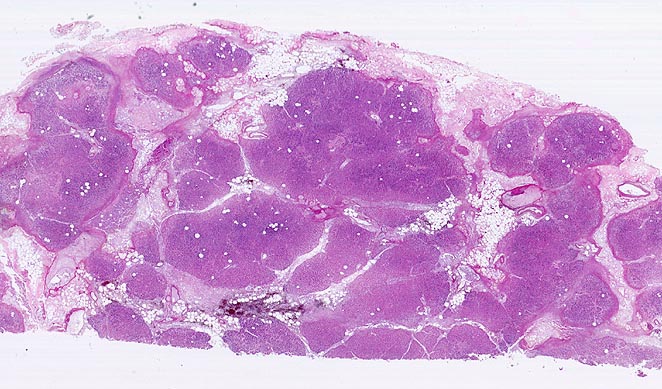

akute Pankreatitis

Pankreas

Pankreasparenchym und Fettgewebe werden von unregelmässigen Nekrosestrassen durchzogen. Bevorzugt ist das interlobuläre Fettgewebe von den autodigestiven Nekrosen betroffen. Die Nekroseareale werden gegen aussen begrenzt durch einen feinen hämorrhagischen Randsaum. Zentrale Parenchymanteile (violett) sind noch vital.

Bekannter Ethylabusus. Nach einem Alkoholexzess kam der Patient wegen heftigster epigastrischer, in den Rücken ausstrahlender Abdominalschmerzen und orthostatischer Hypotonie auf die Notfallstation. 60 Stunden nach Spitaleintritt entwickelt der Patient ein Multiorganversagen und verstirbt.